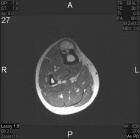

21 year old male with increasing leg pain and enlarging mass for three years

Zoom image: Radiological image Radiological image.